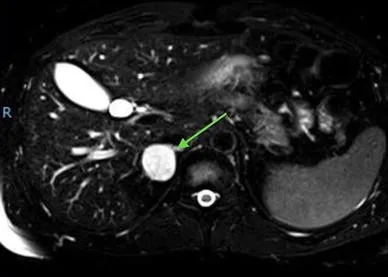

- Diagnosis: ↑ 24-hr urinary metanephrines and vanillylmandelic acid (VMA). Plasma-free metanephrines are also highly sensitive. CT/MRI to localize.

- Imaging: CT or MRI to localize tumor; MIBG scan for extra-adrenal or metastatic disease.